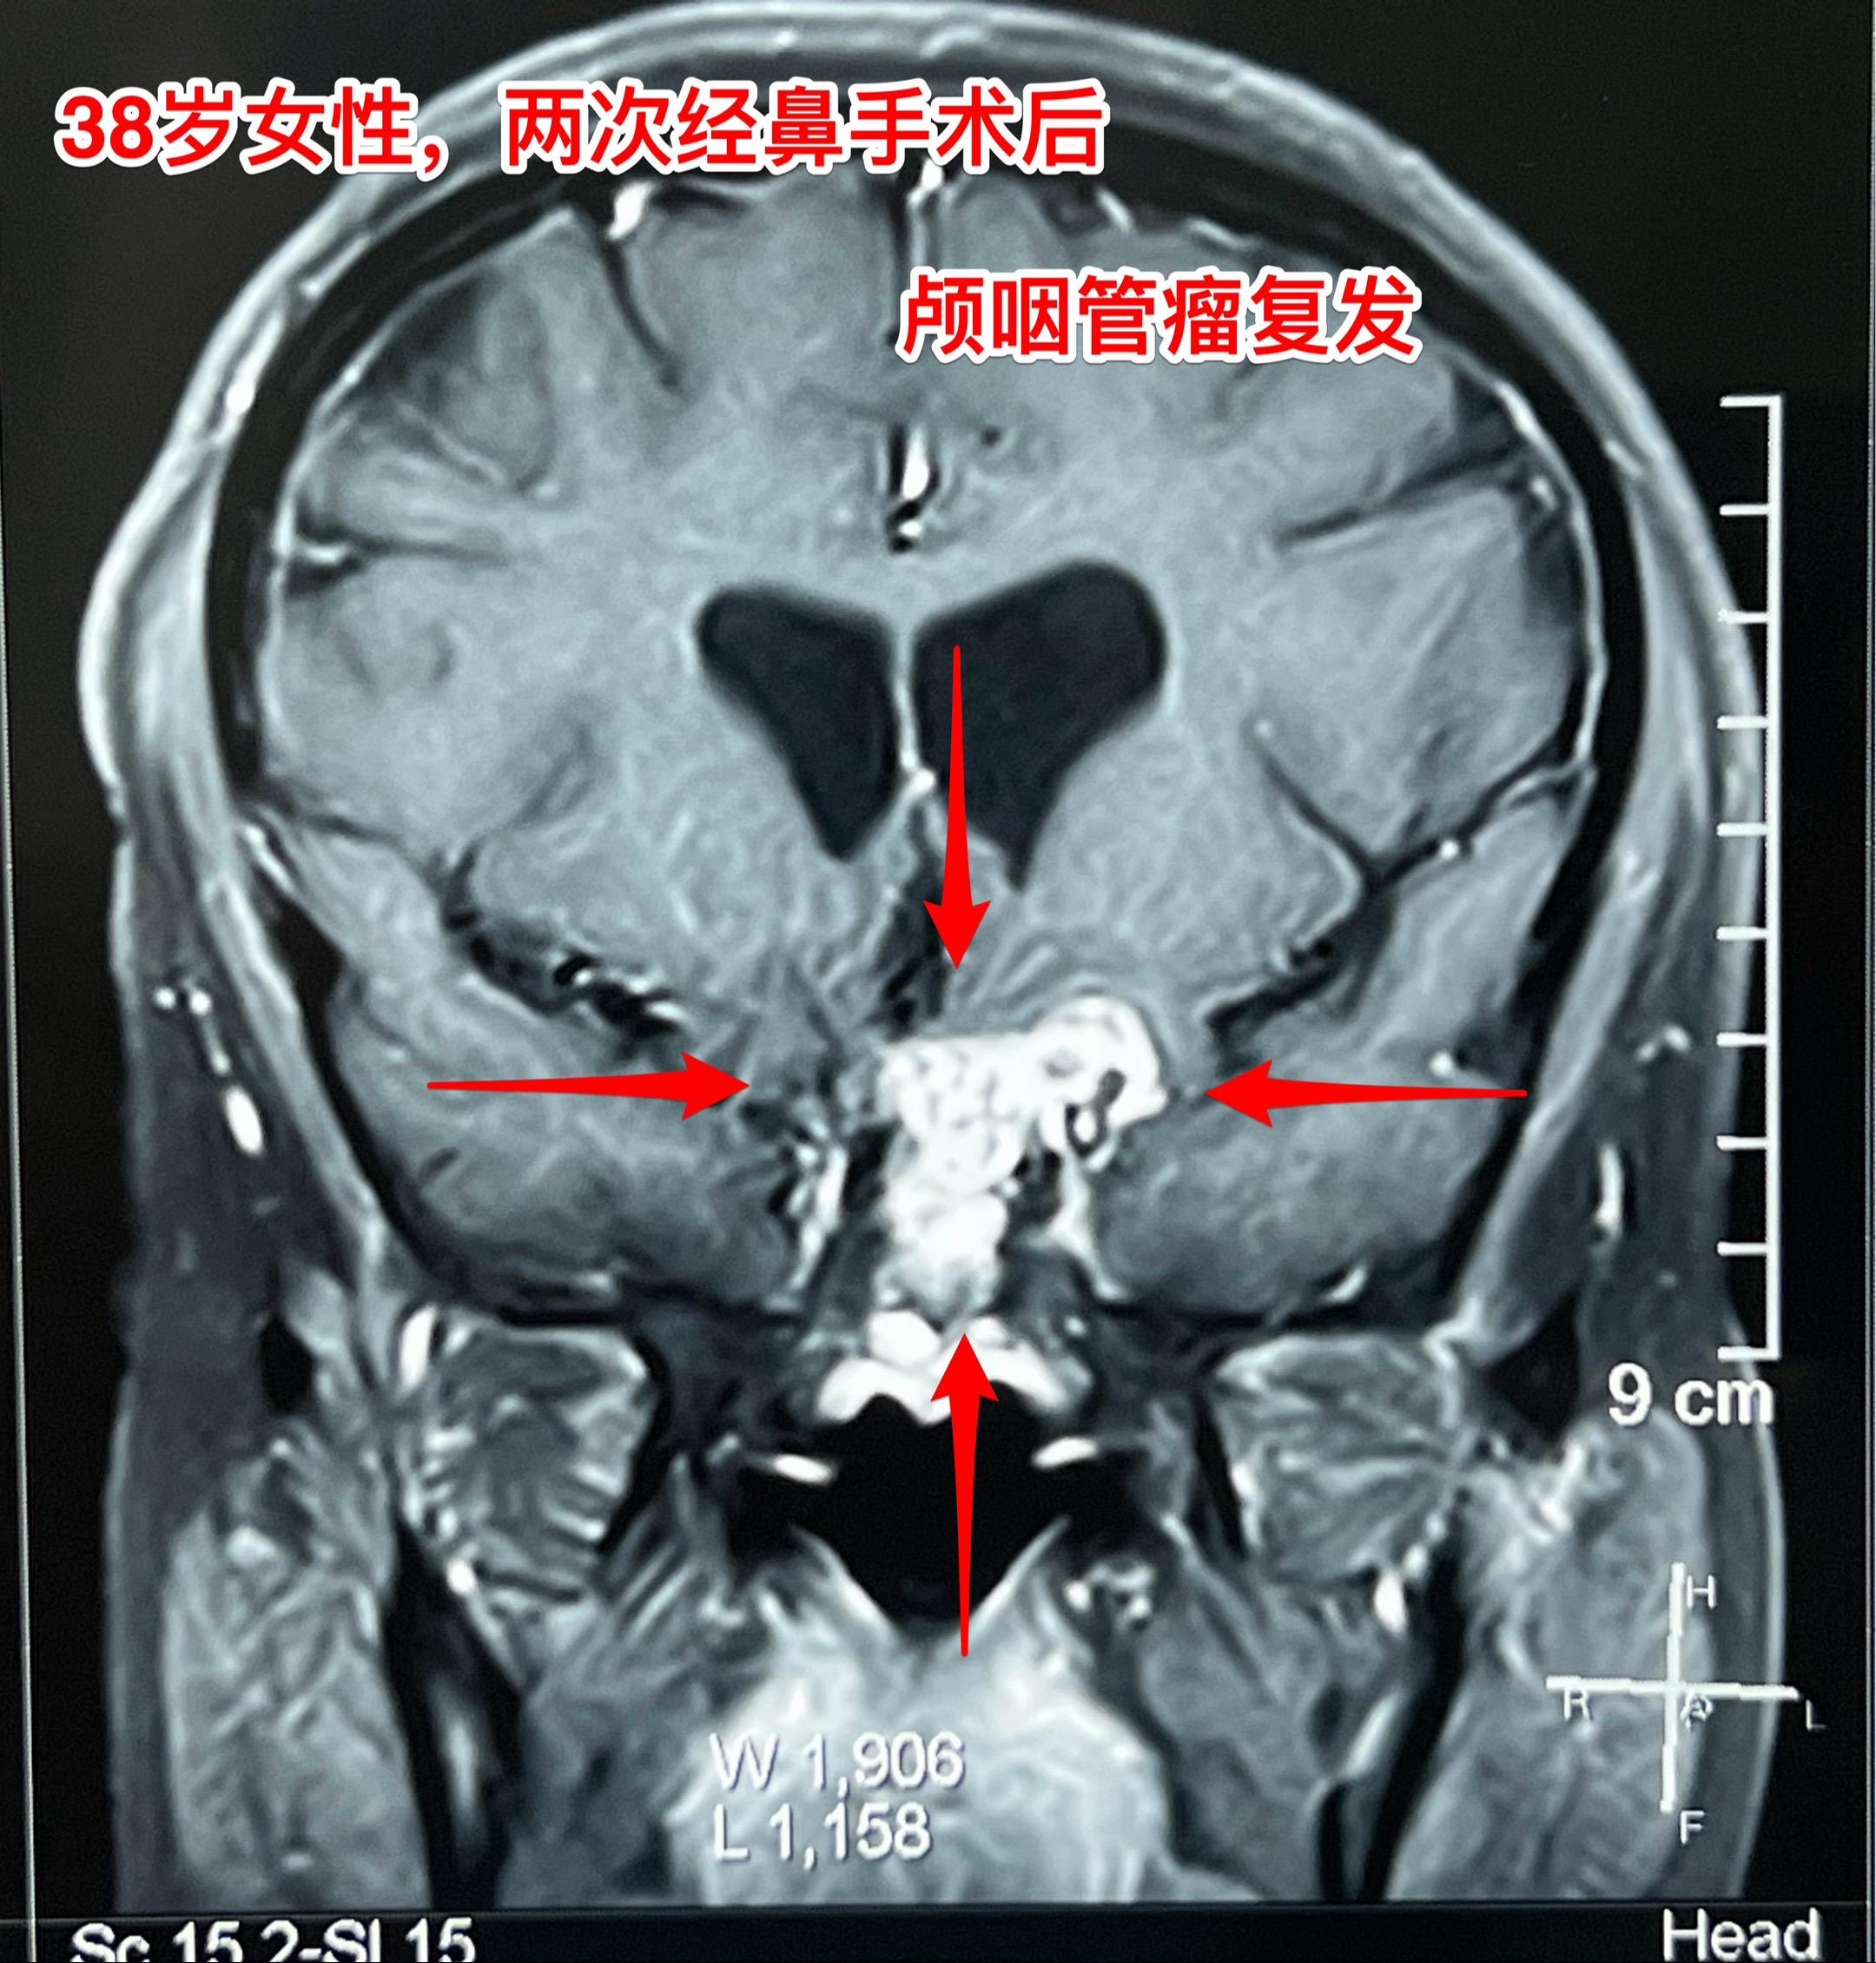

昨天的第四个手术(经鼻复发颅咽管瘤)昨日第四个完成的手术,是38岁女性,因为颅咽管瘤在北京某军医院先后作了两次经鼻内镜手术切除肿瘤。过年后发现肿瘤又复发了,见图。病人的左眼视力很差,属于无效视力。 手术结束时已是今日凌晨了!肿瘤从垂体窝向左侧生长,得到完全切除! 今日头部CT结果是满意的,病人从ICU转回了普通病房。希望肿瘤不再复发。